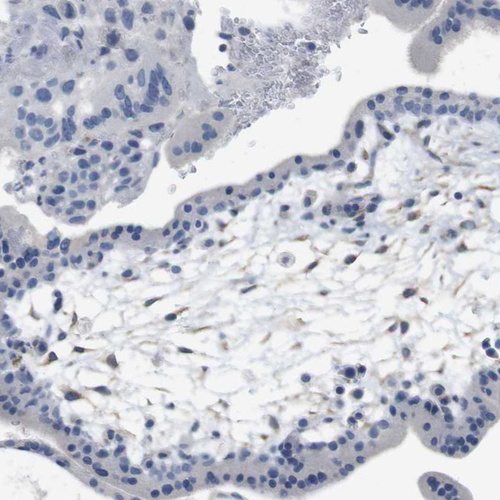

Immunohistochemical staining of human cerebral cortex shows weak to moderate cytoplasmic positivity in neurons.